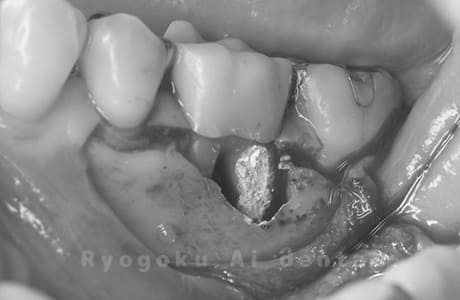

Case04

-

- 原因

- 右下6番パーフォレーション

- 治療内容

- パーフォレーションリペア

- 治療費用

- ¥66,000

右下奥歯が他院で行った治療後、腫れが引かないとのことでご来院された患者様です。近心根の遠心壁にパーフォレーションを認めたため、外科的にパーフォレーション部の修復を行いました。経過良好です。

<リスク・副作用>

手術後は痛み、腫れ、痺れ、青あざなどの副作用が生じます。痛みは痛み止めを処方しますが、腫れ、青あざは1週間程度生じる場合があります。また、部位によっては神経の走行が複雑で、痺れが残り、長期的にお薬を処方する場合があります。